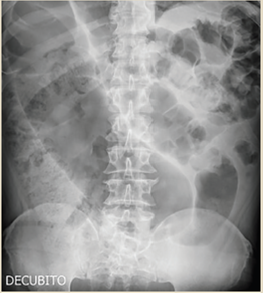

Paciente del sexo masculino, de 79 años, inició su padecimiento actual con estreñimiento de 10 días de evolución; se agrega náusea, vómito, distensión y dolor abdominal. Antecedentes relevantes: diabetes mellitus tipo 2 en control, negó antecedentes quirúrgicos; antecedentes de trauma abdominal cerrado durante la infancia posterior al cual presentó varios cuadros de distensión, y dolor abdominal difuso y estreñimiento crónico. A la exploración física dirigida se observó distensión abdominal, silencio abdominal, se palparon impresiones aparentemente de asas intestinales predominantemente en flanco e hipocondrio izquierdos; doloroso a la palpación profunda, con abdomen en tabla, signo de rebote no valorable, hipertimpanismo a la percusión. Estudios paraclínicos reportaron acidosis metabólica leve con déficit de base. Las radiografías de tórax y abdomen evidenciaron distensión importante del colon transverso hasta el ángulo esplénico e incremento del patrón de distribución aérea, así como colon sigmoides dilatado y desplazamiento e interposición de asas sobre colon ascendente y ángulo hepático con niveles hidroaéreos (figuras 6 y 7). Se integró diagnóstico de probable megacolon secundario a vólvulo intestinal complicado, con datos de peritonitis e isquemia intestinal. Se indicó laparotomía exploratoria de urgencia; como hallazgos quirúrgicos se obtuvieron colon descendente y sigmoides distendidos, diámetro máximo de 20 cm y 100 cm de longitud (figura 8), laxitud marcada de sus medios de fijación, vólvulo a nivel de transición de colon descendente y sigmoides, así como múltiples adherencias en el trayecto del colon transverso, descendente y sigmoides (figura 9). Se realizó procedimiento de Hartmann con colostomía de colon transverso.

Figura 6 PA de tórax. Distensión importante de colon transverso y ángulo esplénico, incremento del patrón de distribución aérea, desplazamiento de hemidiafragma y hemitórax izquierdo

Figura 7 AP de abdomen. Colon sigmoides dilatado, desplazamiento e interposición de asas sobre colon ascendente y ángulo hepático, niveles hidroaéreos